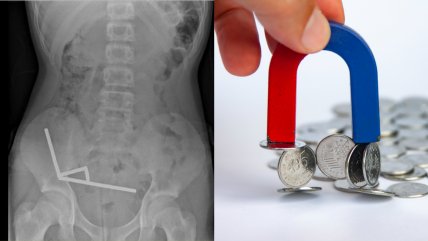

Salud Cirugía pionera en el Reino Unido: imanes y un clavo interno corrigieron malformación ósea en un niño